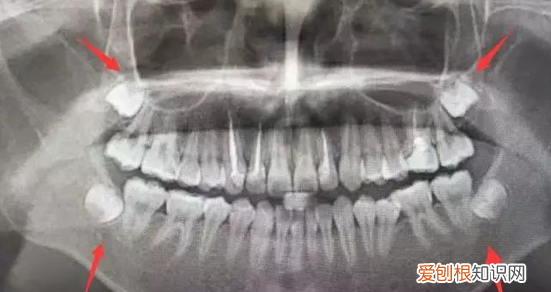

智齿是指人类口腔内,牙槽骨上最里面的上下左右各一的4颗第三磨牙 。因为这4颗第三磨牙正好在20岁左右开始萌出,此时人的生理、心理发育接近网成熟,于是被看作是“智慧到来”的象征,故称它为“智齿”,是口腔最靠近喉咙的牙齿 。

4颗智齿也不是都必然会长全,某些人的智齿可能只长1~2颗,有的智齿甚至长到一半就不再生长,这种情况称为智齿阻生,即阻生齿 。智齿的位置从门牙正中开始,由一侧门牙向里数牙齿数目,如果有第八颗牙,它就是智齿 。

为网什么智齿会长不出或长歪?在青春后期,颌骨发育到接近成人大小 。但有些人颌骨还不够大,没有足够位置供智齿萌出,智齿就会阻生在颌骨内,向其他方向生长,可能只有部分牙冠露出牙龈,或完全埋在颌骨里,牙根可能变形或向上颌窦或下颌骨神经所在部位生长 。

由于空间不足,阻生的智齿就向各种不同的方向生长,一般与邻近牙齿形成角度,可以向着邻近牙齿生长(近中阻生),远离邻近牙齿生长(远中阻生),也可以水平或垂直阻生,甚至倒置阻生 。